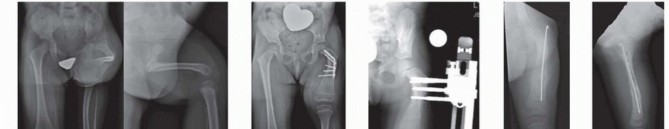

Before lengthening, hip stability should be determined radiographically. The best indicator is the CE angle. If the CE angle is less than 20 degrees, a Dega osteotomy should be performed before lengthening. In addition, the AI should be less than 30 degrees. If the CE angle is borderline 20 degrees but the AI or inclination of the sourcil is high, it is better to err on the side of caution and perform a Dega osteotomy ( FIG 6 ).

Coxa vara should be corrected before lengthening if the neck-shaft angle is less than 120 degrees. When coxa vara and hip dysplasia are present and when the coxa vara is severe, the superhip procedure is performed. The pelvic and femoral osteotomies should be performed 12 months before the first lengthening. The superhip procedure is a

comprehensive surgery to correct the proximal femoral and hip deformities with concurrent soft tissue releases. Illustration 10 for Treatment for Congenital Femoral Deficiency: What You Need to Know Illustration 11 for Treatment for Congenital Femoral Deficiency: What You Need to Know FIG 5 • A. Articulated AFO prosthesis. B. Plantar flexion and dorsiflexion. The ankle motion aids with walking. Illustration 12 for Treatment for Congenital Femoral Deficiency: What You Need to Know FIG 6 • Paley type 1a CFD with dysplastic acetabulum. The CE angle is 11 degrees. The patient underwent a Dega osteotomy. At the conclusion of a successful superhip procedure, the proximal femur has been anatomically and biomechanically reconstructed and the delayed ossification of the femoral neck has ossified. The femur can now be reclassified from 1b to 1a. This ossification occurs within 3 to 12 months of the superhip procedure (often aided by the insertion of BMP). Lengthening is usually not performed in type 1b cases until they convert to type 1a. If lack of full ossification of the femoral neck or subtrochanteric region persists, despite the superhip procedure, repeat insertion of BMP is indicated. As a final measure to allow lengthening to begin in such hips at risk, the external fixation can be extended to the pelvis to protect the hip.